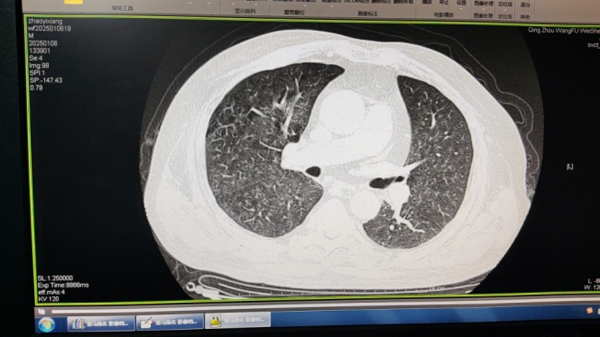

病例:赵某 ,男,51岁,从事电焊工作10年余,在不通风车间工作时仅佩戴普通口罩,于2024年12月25日首次到本院就诊,主诉胸闷、咳嗽1月,活动后气短,负重运动后加重,病情逐渐加重。以下是其首次2024年12月25日及两次复查2025年1月6日、2025年4月23日胸部CT平扫影像资料,双肺散在细小结节状阴影,经三甲医院会诊后诊断为“电焊肺”。

2024年12月25日